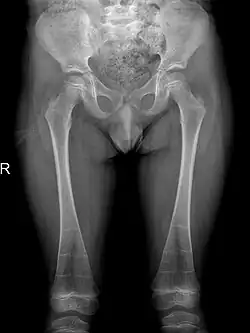

A frontal radiograph showing metaphyseal flaring of both femora[19]

Sclerosis of epiphyses, diaphyses, and metaphyses with increased radiolucency are key characteristics of the disease.[18] In addition, mottled metaphyseal sclerosis and widening are also present in patients.[4][9] Development of irregular patchy sclerosis along the bone can also be identified,[9] as well as metaphyseal flaring evolve towards Erlenmeyer flask deformity with nonuniform patches of sclerosis, which are especially prevalent in older patients.[10]

The metadiaphyses, a portmanteau of the metaphysis and diaphysis,[20] are bulbous and expanded with bowing and relative radiolucency. The expanded regions are also sclerotic and gives the characteristic bone-in-bone appearance.[4]